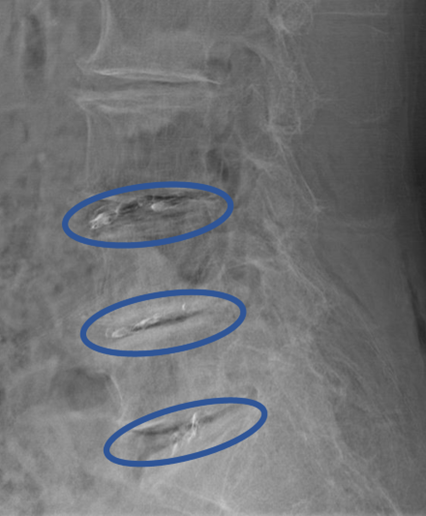

L1/2: 椎間板変性症

L2/3: 椎間板変性症

L3/4: 椎間板変性症、両椎間孔狭窄

L4/5: 椎間板変性症、左椎間孔狭窄

L5/S: 椎間板変性症、椎間板ヘルニア、左椎間孔狭窄

以上の事が画像上認められます。

L3/4,4/5,5/sに

椎間板変性症、椎間板ヘルニア、椎間孔狭窄を認め、主症状の原因の可能性が高い。

DiscoGelを入れた後の画像になります。